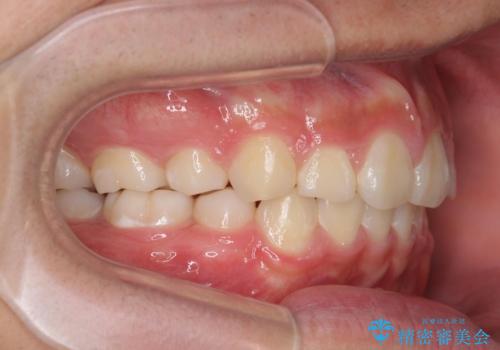

- 放置してしまった右下の歯の欠損治療を希望され来院されました。

しっかりと噛んで、食事を楽しむためにブリッジではなくインプラント治療を希望されました。

放置することで倒れこんできてしまった、右下最後方臼歯をインプラントを用いた小矯正を行いより清掃性を高める治療を計画します。

倒れた歯を小矯正を用いて起こすことで、清掃性を確保しインプラントにとっても長期的な予後を期待することができます。